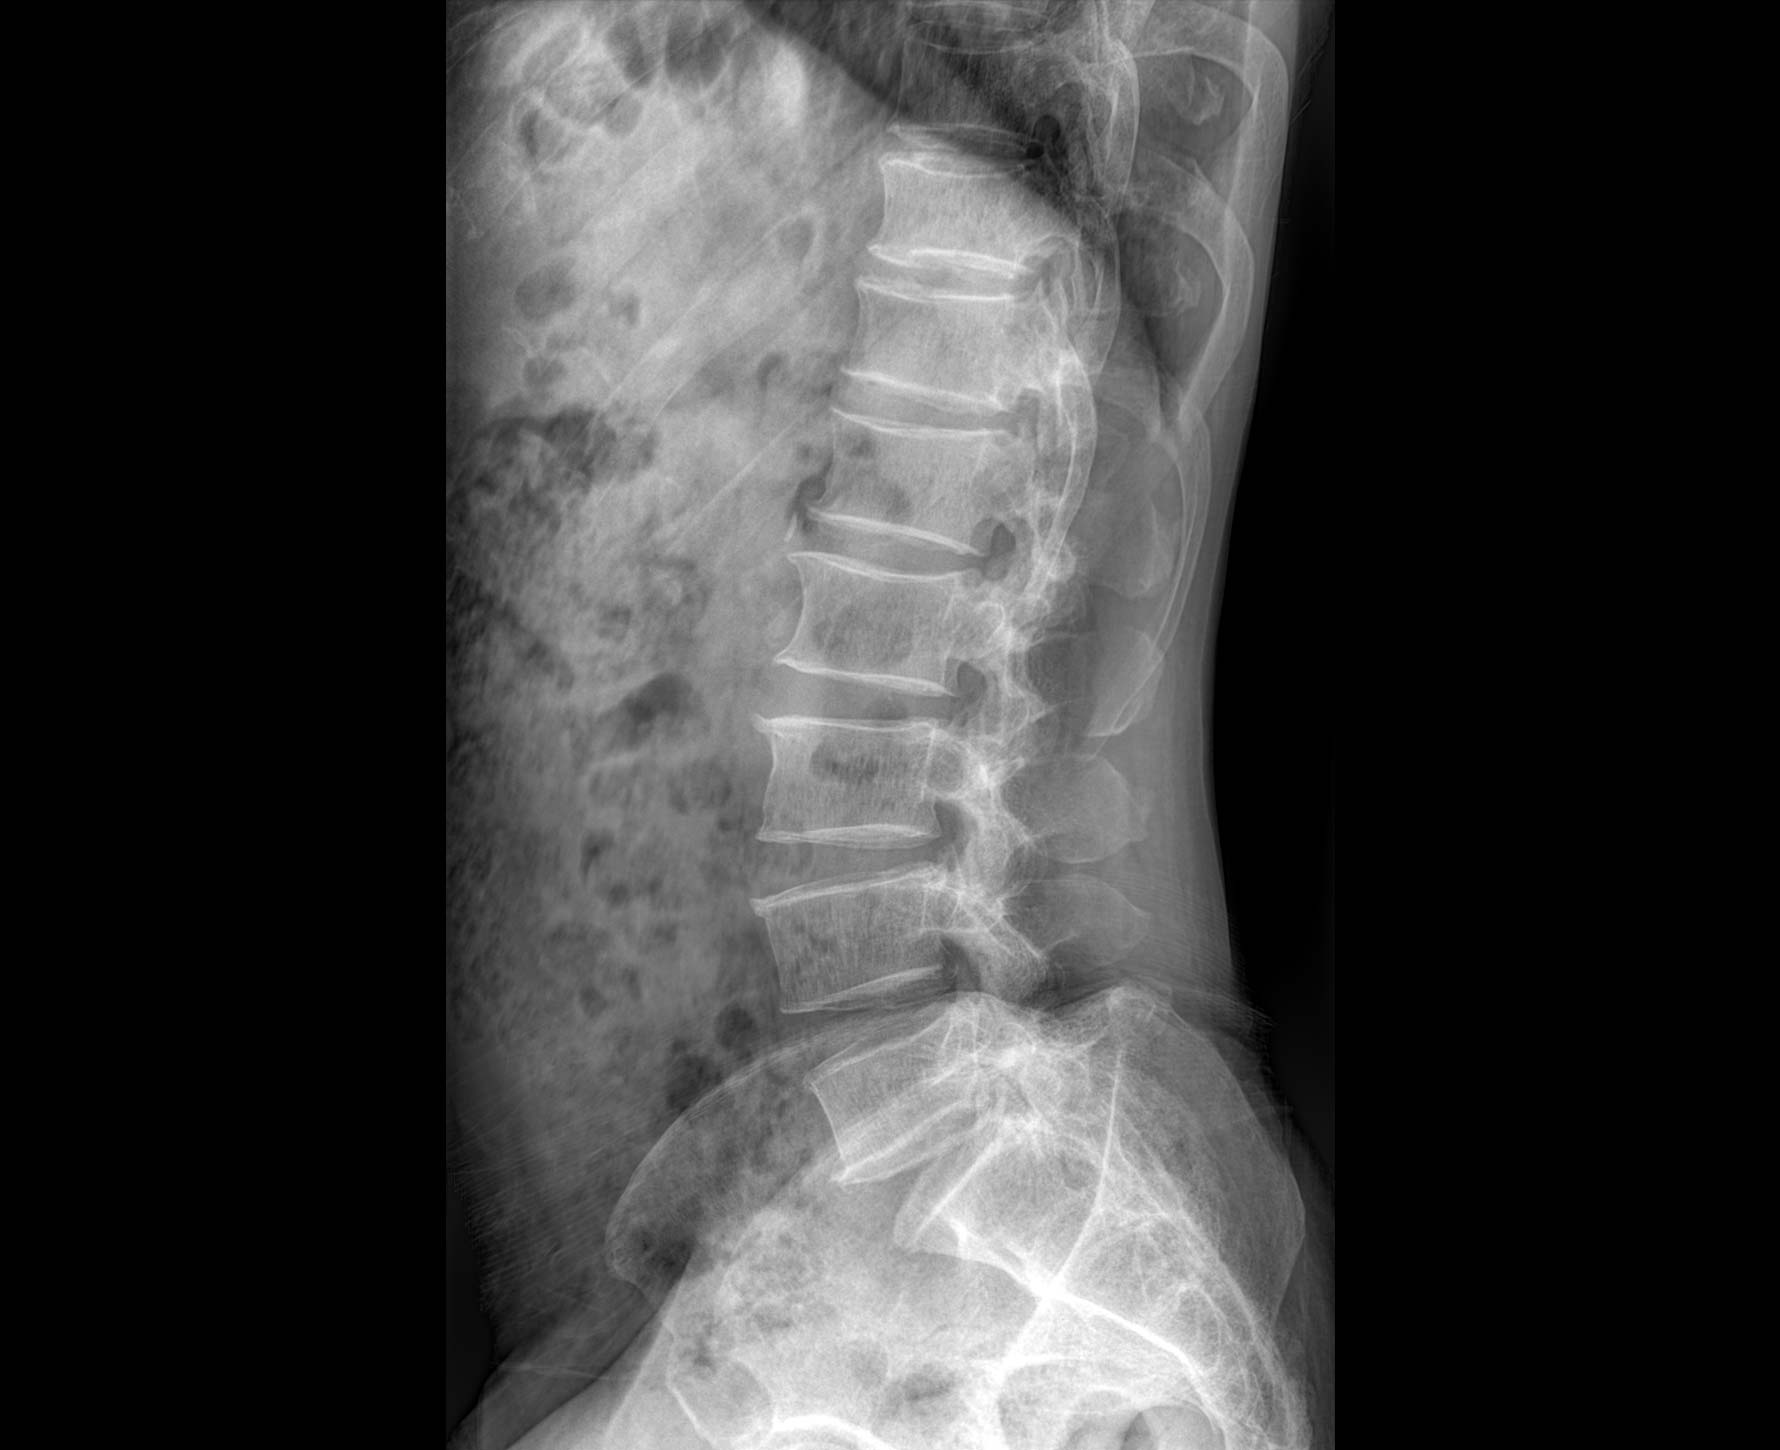

• 透视

适用于全身各

部位透视检查